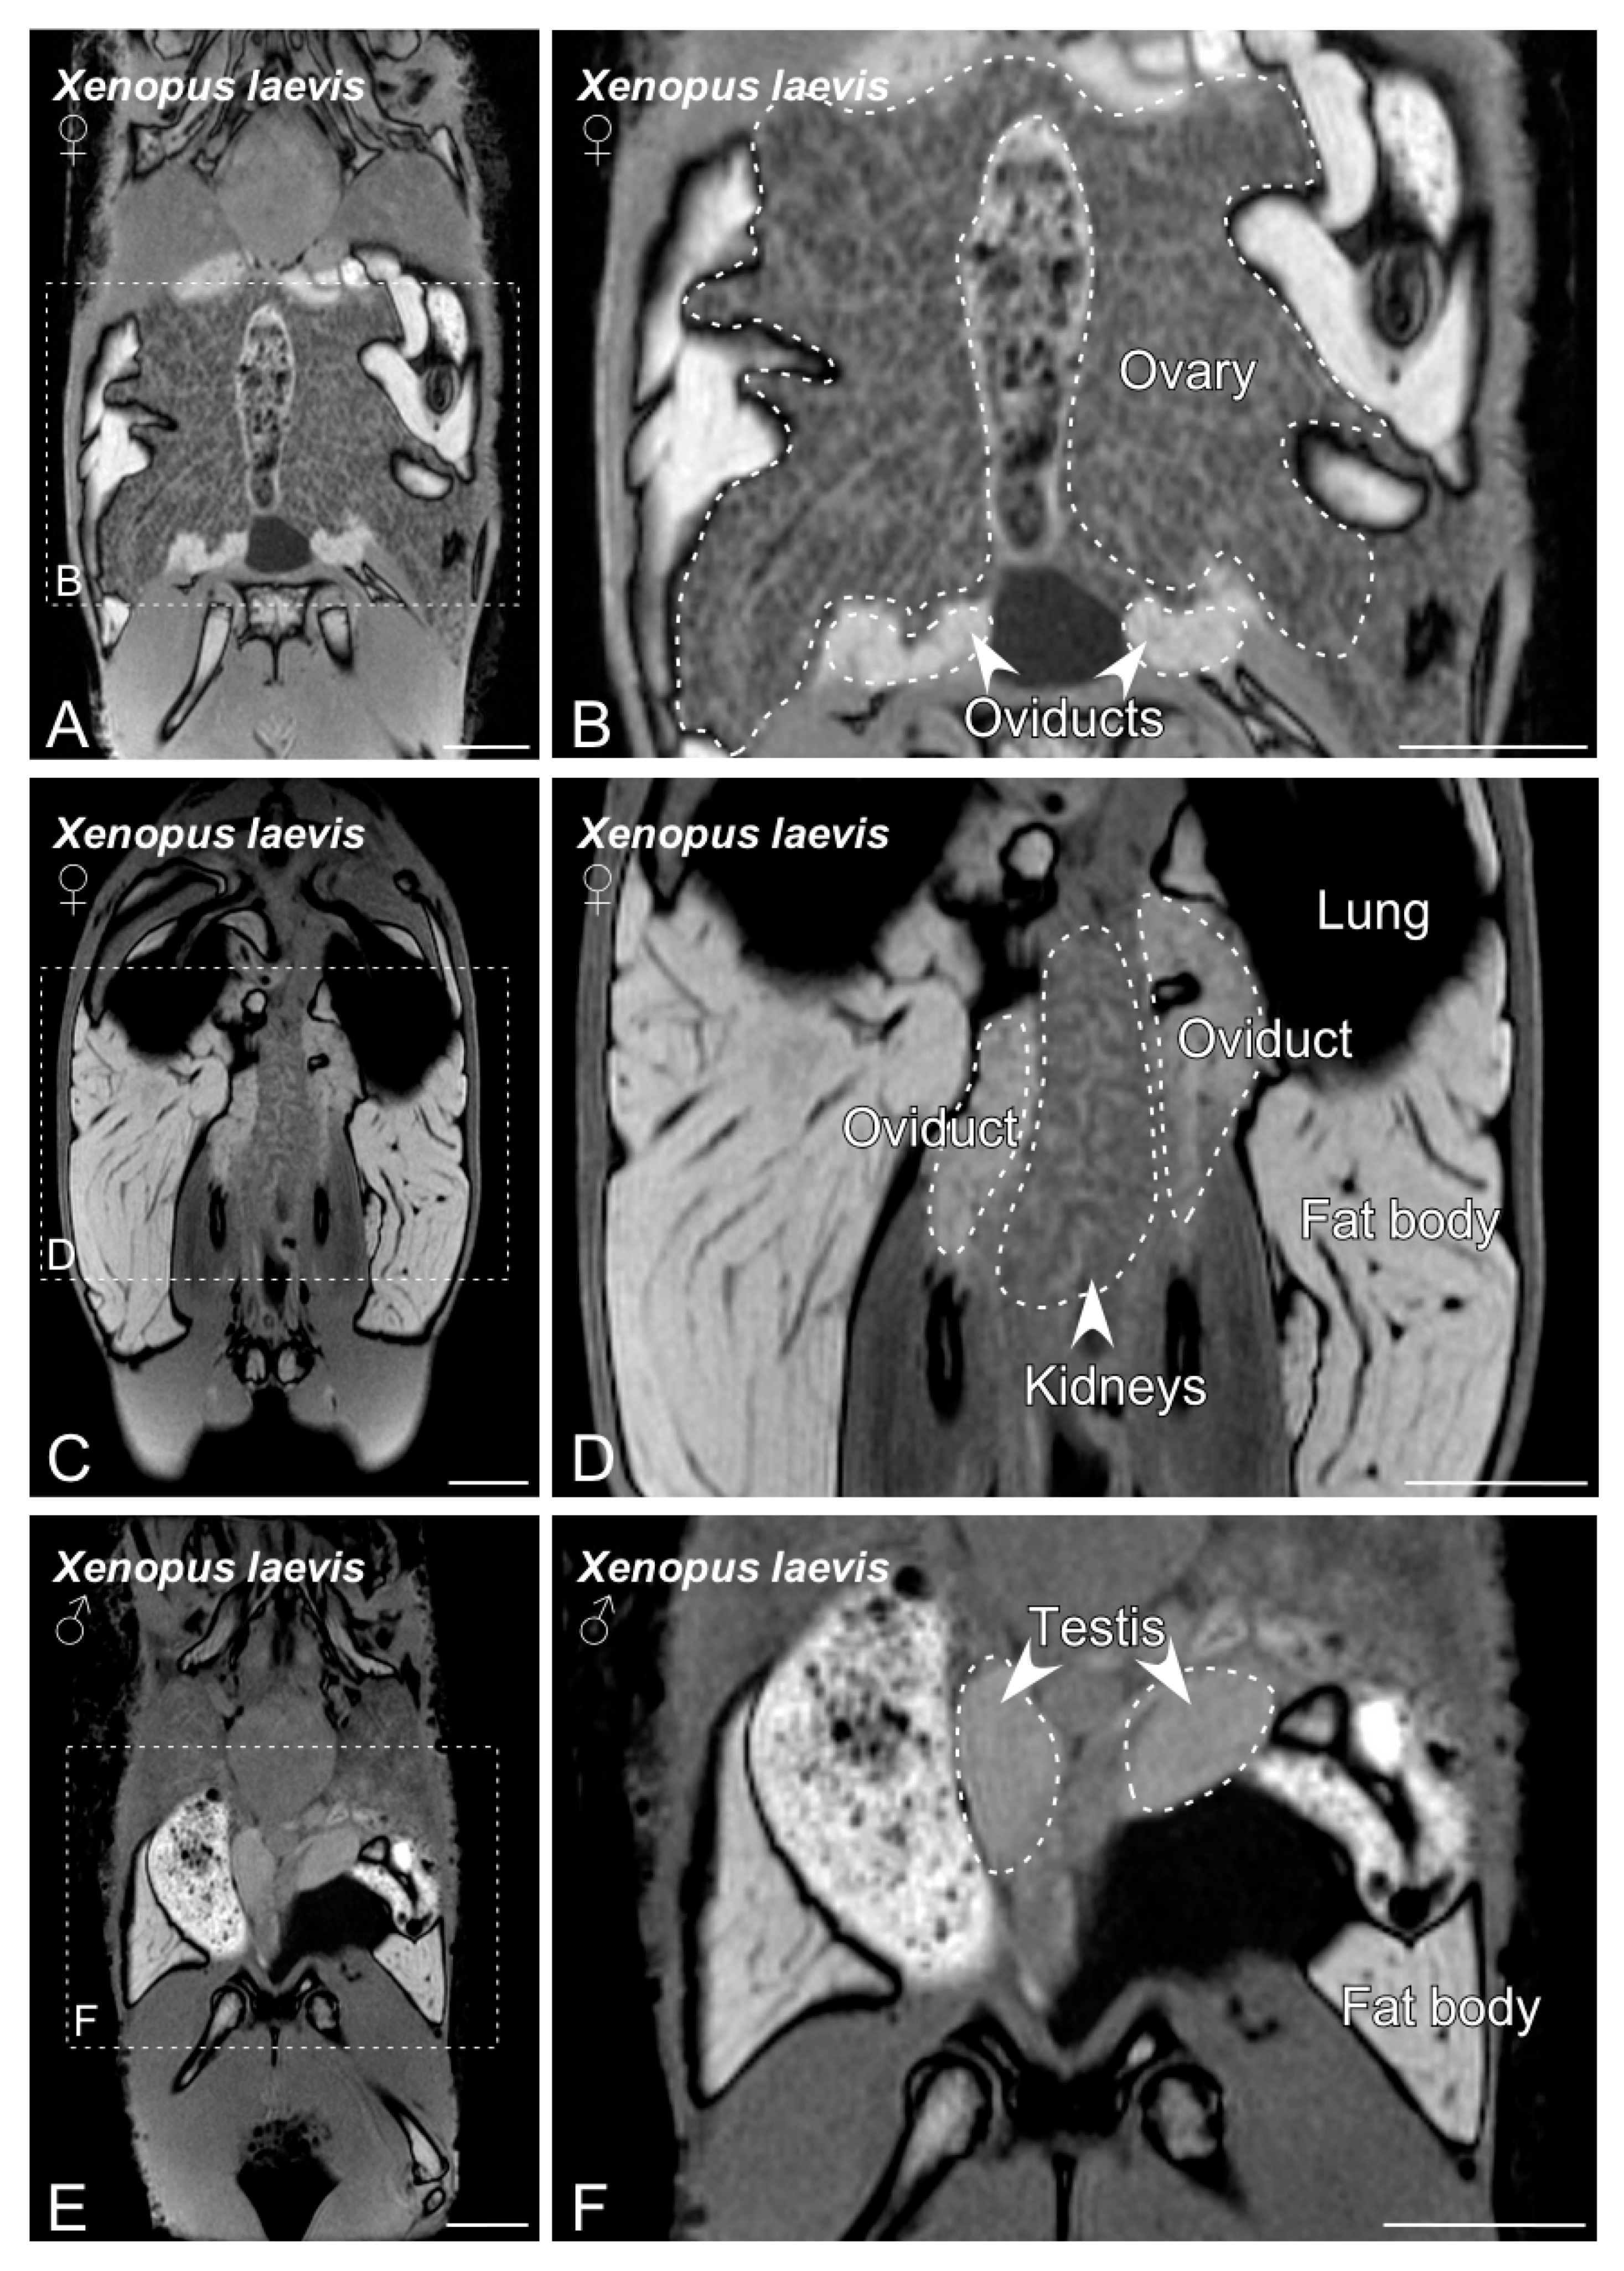

3.1. BT-MRI